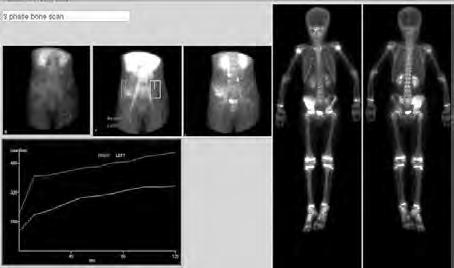

2.6.4 Radionuklidové metody (Daniela Chroustová) 35